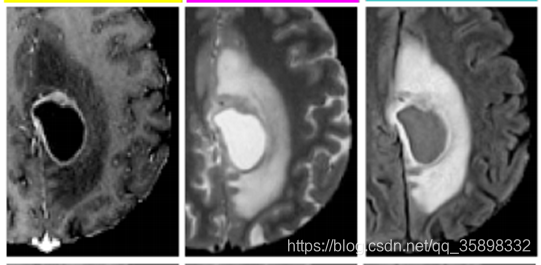

这个数据集扫了不同序列的MRI(描述里面写的4个,文章中给的图是3个),示意图如下:2000 cases (2020年 660 cases)